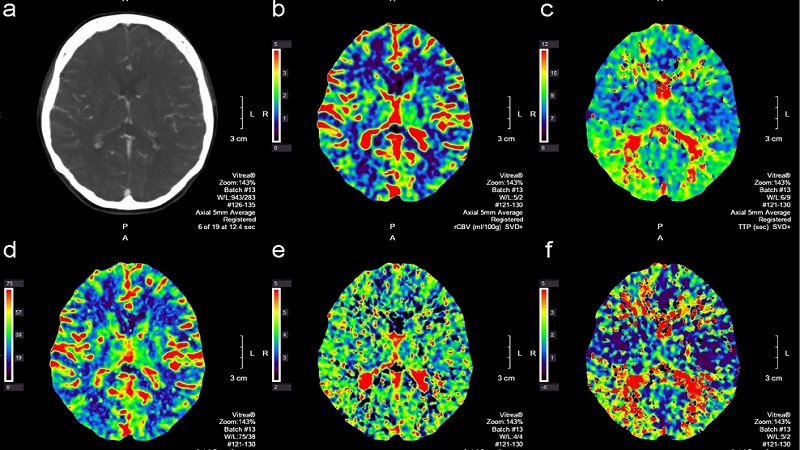

Chụp cắt lớp vi tính tưới máu não (CT perfusion) là kỹ thuật sử dụng thuốc cản quang có thành phần chính là iod để tiêm vào mạch máu, sau đó chụp lại bằng máy chuyên dụng để khảo sát khả năng tưới máu của mô não. Khi thực hiện kỹ thuật này, các chuyên gia y tế có thể nhìn rõ đường đi của mạch máu, xác định chính xác lưu lượng mạch máu não và đưa ra những đánh giá ban đầu về tình trạng tổn thương nhu mô não ở người bệnh.

Khi quan sát kết quả chụp CT qua hình ảnh 2D hoặc 3D, bác sĩ có thể phân biệt rõ vị trí tổn thương và vùng mô não thiếu máu nhưng vẫn có thể phục hồi được, từ đó đưa ra liệu pháp can thiệp kịp thời. Ngoài ra, đây còn là xét nghiệm hình ảnh giúp chẩn đoán nhiều bệnh lý liên quan đến mạch máu não và u não.